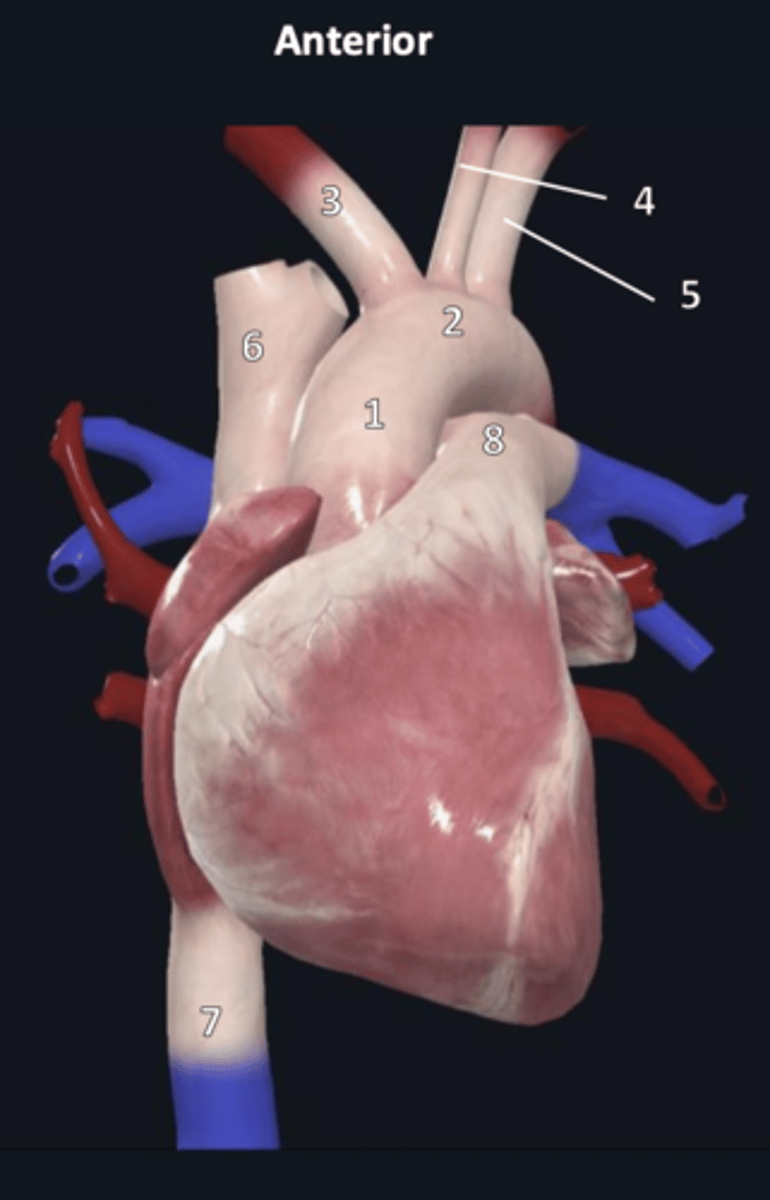

ascending aorta

1

aortic arch

2

brachiocephalic trunk

3

left common carotid artery

4

left subclavian artery

5

superior vena cava

6

inferior vena cava

7

pulmonary trunk

8